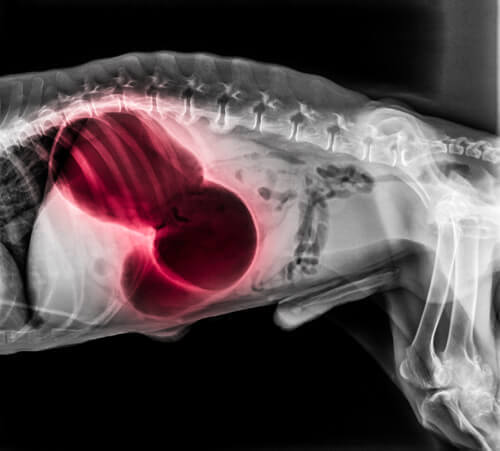

I hjärta och lungor

Blodproppar i hjärtat eller lungorna kan föra med sig olika allvarliga systemiska symptom, som exempelvis att hunden svimmar, får andnöd eller blir förlamad.

Hundens tandkött kan också blekna och hunden kanske inte kan sova. Den kan också börja hosta upp blod. När det drabbar lungorna så är det vanligtvis dödligt.